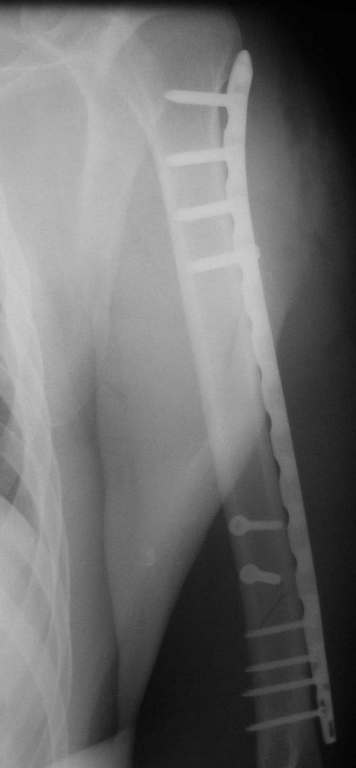

Позвольте привести пример из собственной московской практики в поддержку тактики, приведенной в данном примере. Пациент переведен из одной из московских клиник на 3 сутки после сквозного огнестрельного ранения плеча(пистолет)с ушитыми узловыми швами и дренированными резиновым выпускником ранами на внутренней поверхности плеча с умеренным серозногнойным отделяемым и похожей раной на задненаружной поверхности грудной клетки (пуля прошла через плечо и остановилась в мышцах спины). Также имелись реактивный локтевой бурсит и нейропатия локтевого нерва. При поступлении были сняты швы, начата антибиотикотерапия. Через сутки после травмы пациент прооперирован: выполнена повторная хирургическая обработка ран плеча и грудной клетки. Через отдельные доступы на наружной поверхности плеча произведен минимально инвазивный остеосинтез плечевой кости блокируемой метадиафизарной пластиной. Пациент выписан на 4 сутки после операции. Дальнейшее течение гладкое, все раны зажили первичным натяжением. Еще раз пациент был госпитализирован через 4 месяца после операции с переломом этого же плеча на границе средней и дистальной третей: коллеги по криминальному ремеслу применили к нему слишком жесткие меры убеждения. Выполнен остеосинтез путем замены и добавления винтов в дистальной части пластины. Госпитализация 2 суток. К сожалению, последние снимки не сохранились.

Красиво и быстро?! - две пластины + 18 шурупов.

Идеальная репозиция?! -На снимочке A-P проeкции видна "зазубрина" по суставной поверхности, латеральный снимок - тоже не идеально.

Множество мелких FB в кости.